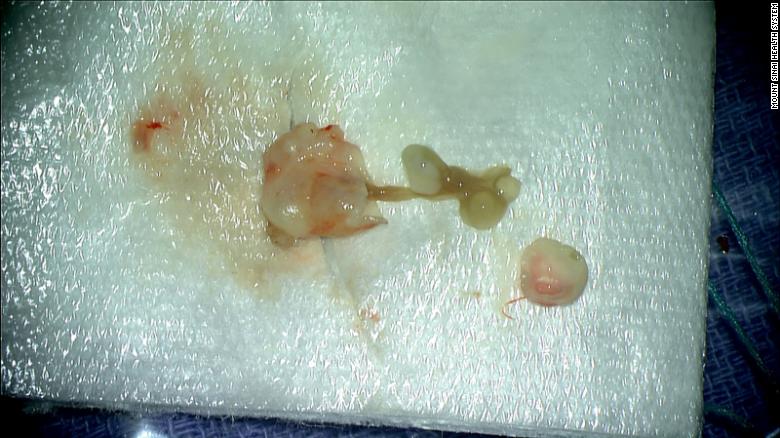

În timpul acestei lupte, severitatea simptomelor vizuale i-a determinat pe medici să facă un RMN, unde au găsit ceea ce se credea că este o tumoare care provoacă durerea. La îndepărtarea leziunii, au descoperit că masa nu era o tumoare, ci mai degrabă un chist plin de larve de tenie!

După îndepărtare, simptomele femeii au încetat și nu a mai avut nevoie de niciun tratament suplimentar. Această afecțiune parazitară, cunoscută sub numele de neurocisticercoză, apare după ingestia accidentală de alimente sau de apă contaminate cu ouă Taenia solium (sau tenie de porc).